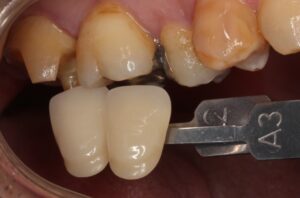

後は歯型を取り、

歯の色をチェックしていきます。

色見本で歯の色を記録して、

その歯に合った色のセラミックインレーを歯科技工士に製作してもらいます。

セラミックがセットされました。

歯の色が綺麗に仕上がっています。

治療した所が分からないですね。